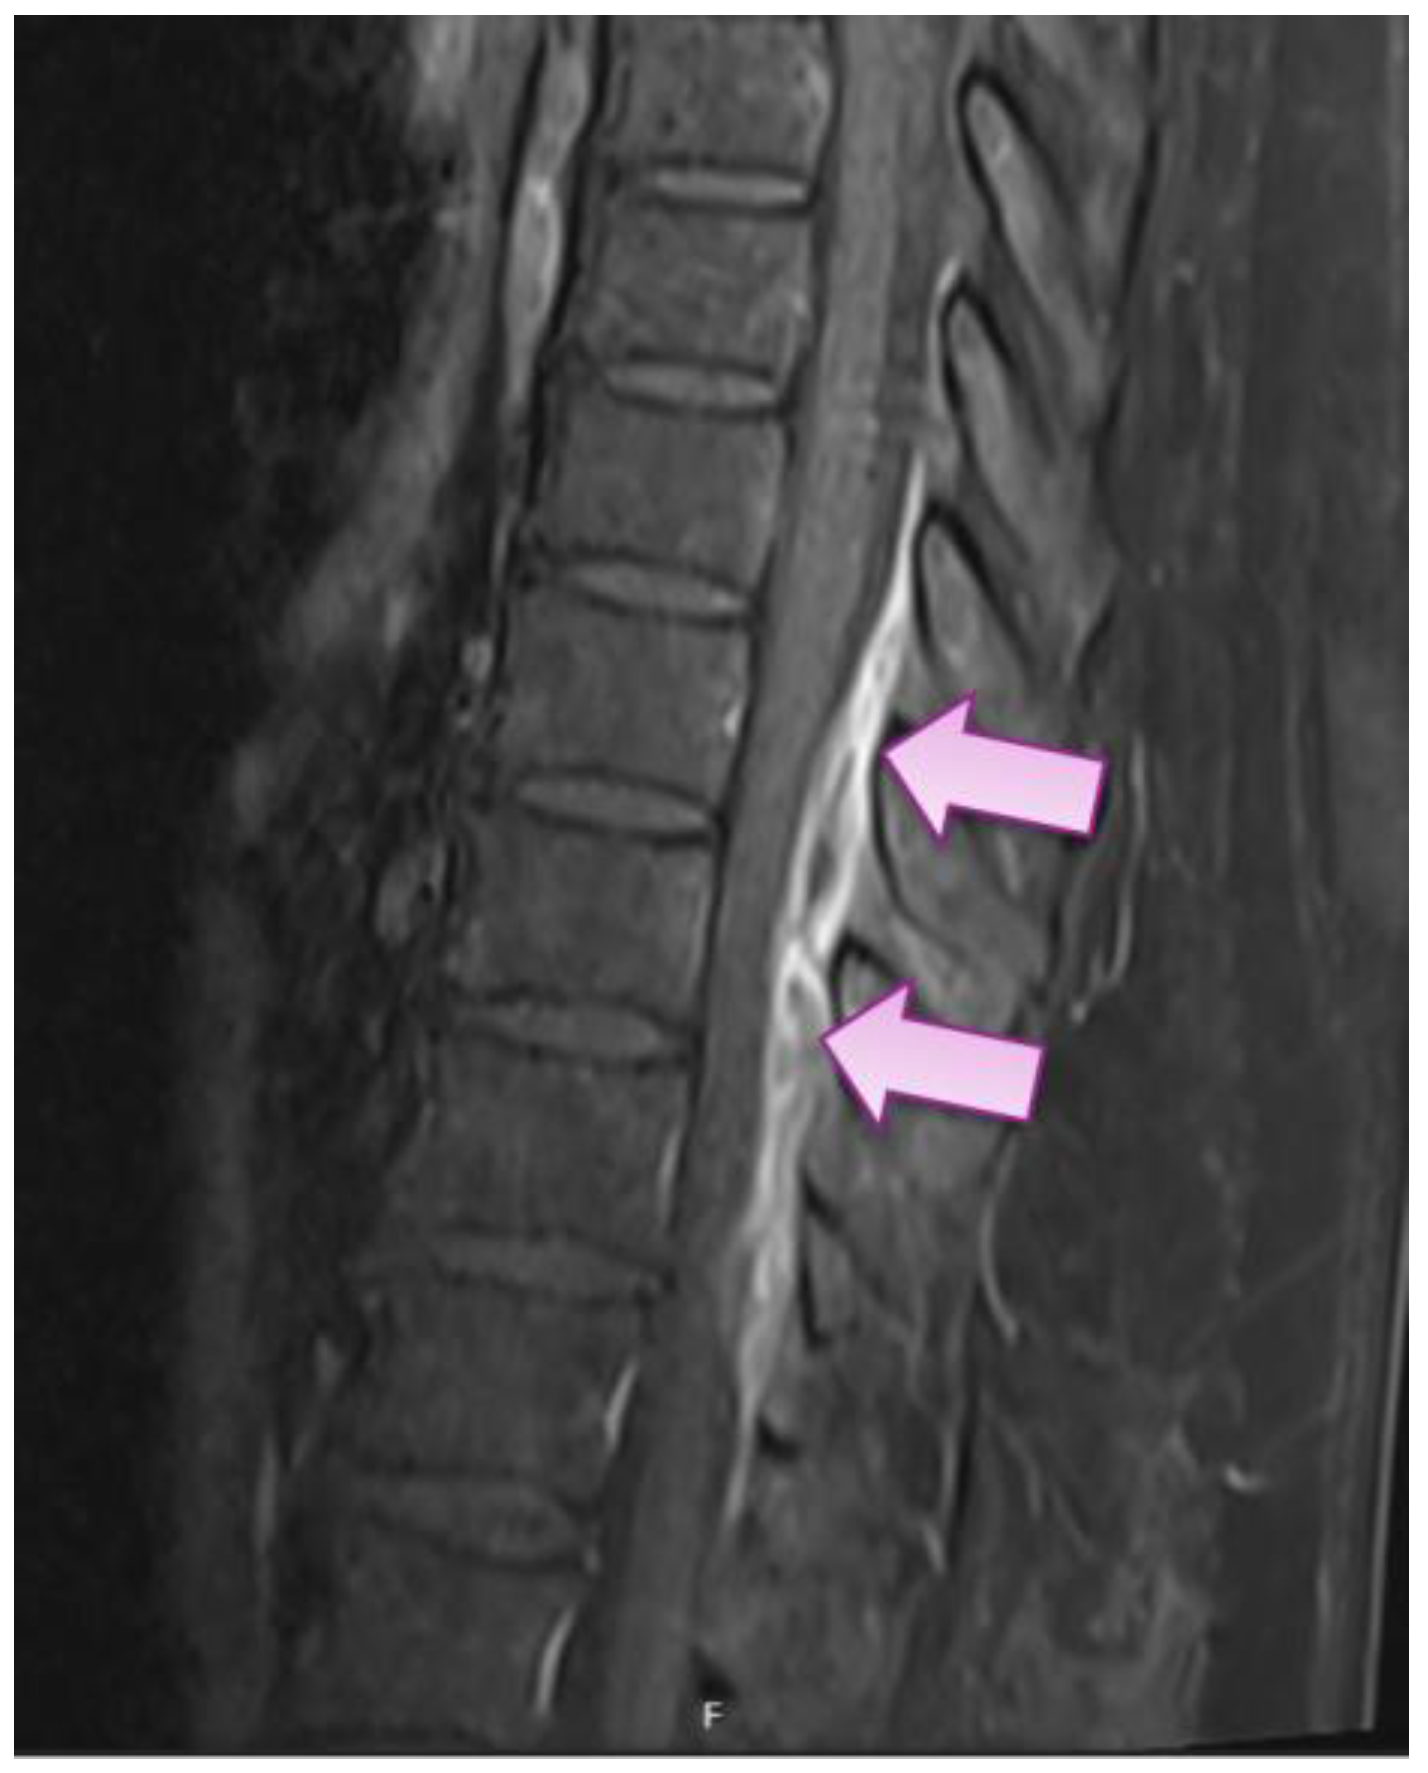

On Day 5, the patient complained of new onset back pain at the level of the 12th thoracic vertebra (Th12) of sharp quality during movements with intensity of 4 to 5 out of 10, which was managed with non-opioid analgesics. On Days 8 and 9, the patient had repeated episodes of febrile body temperature, accompanied by leukocytosis in full blood count on Day 7, although her CRP had dropped from 141.8 to 6.6. mg/L (see Table 1). Due to unexplained febrility and leukocytosis, blood cultures through two peripheral sites were performed on Day 10, with subsequently positive result showing methicillin-sensitive Staphylococcus aureus (MSSA) bacteremia (resistant to penicillin G, moderately susceptible to ciprofloxacin, and susceptible to erythromycin, clindamycin, tetracycline, chloramphenicol, linezolid, rifampicin, trimethoprim/sulfamethoxazole, and gentamycin). Because of previously reported allergic reactions to penicillin group antibiotics, the patient started a second-choice treatment with an IV course of vancomycin 1500 mg BID with subsequent serum trough concentration monitoring with a target range of 15 to 20 mcg/mL. Due to back pain associated with unexplained bacteremia, the patient underwent magnetic resonance imaging (MRI) of her thoracic and lumbar spine, which revealed small epidural abscesses within the dorsal epidural space at Th9 to 12 (Figure 2), as well as epidural fat infiltration of 0.4 × 0.8 × 2.2 cm at lumbar vertebra 4–5 (L4–5) and psoas sinister muscle 1.3 × 1.4 × 2.8 cm abscess at L5 level and smaller abscesses in paravertebral muscles at L4–5 level. The patient also had lumbar spondylarthritis, mainly at L4-S1 level, with foraminal stenoses. Testing for alternative causative agents for epidural abscesses, e.g., Mycobacterium tuberculosis, was not performed because MSSA was already established as the cause due to positive blood cultures.

Figure 2.

Sagittal magnetic resonance image showing dorsal epidural infiltration with small abscesses from the upper border of Th9 to Th12 (arrows).